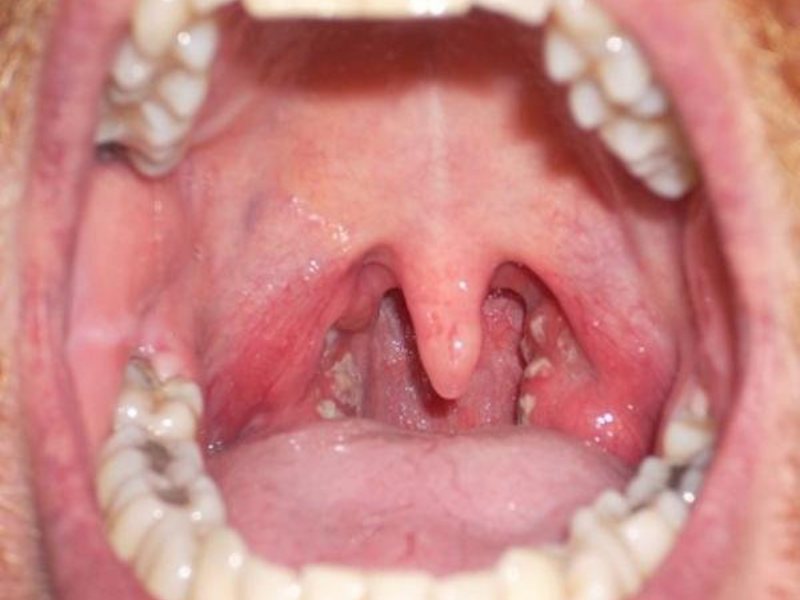

- Ангина подразумевает красное горлышко, увеличенные миндалины, кашель, повышенную температуру. Процесс глотания болезненный, возможен белый гнойный налет на миндалинах.

- Фарингит имеет практически те же симптомы, что и ангина, и на начальной стадии их сложно отличить, это боль при глотании, ощущение комка в горле, кашель, красные стенки и гнойный налет. Но лечить фарингит легче ангины.

- Тонзиллит вызывает воспаление небных миндалин, гнойные образования на них, повышение температуры.

- Скарлатина способствует покраснению не только горла, но и щек, просматриваются воспаленные точки на горле, увеличиваются лимфоузлы.